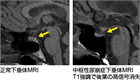

1. 下垂体MRI画像所見は中枢性尿崩症の診断に有用である(推奨度1)